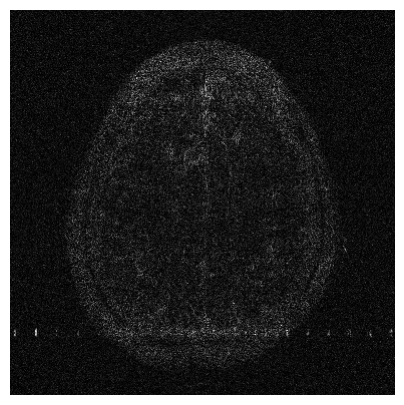

The visual inspection of the images reconstructed (available in Fig. 2) at acceleration factor 4 shows little to no visible difference with the ground truth original image. However, when increasing the acceleration factor to 8, we can see that smoothing starts to appear which leads to a loss of structure as can be seen in Fig. 3.

| T1 PSNR: 38.57 SSIM: 0.9348 | T2 PSNR: 37.41 SSIM: 0.9404 | FLAIR PSNR: 36.81 SSIM: 0.9086 | T1POST PSNR: 38.90 SSIM: 0.9517 |